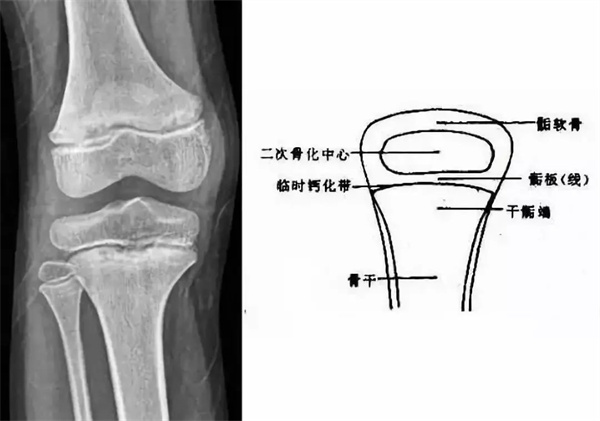

我們都知道,人體的高矮是由骨骼的生長(zhǎng)發(fā)育決定的,特別是下肢長(zhǎng)骨。長(zhǎng)骨呈長(zhǎng)管狀,在長(zhǎng)骨的兩端有一種專管骨骼生長(zhǎng)的骺軟骨,它與干骺端之間有一盤狀軟骨結(jié)構(gòu)稱為骺板(線),在幼兒的X光片上表現(xiàn)為一條較寬的透光帶。(見(jiàn)下圖)

未成年時(shí)隨著年齡的增加骺軟骨端不斷骨化,骨骼就不斷增長(zhǎng)。當(dāng)骨骺線完全閉合時(shí)骨骼就停止生長(zhǎng),個(gè)子也就不再增長(zhǎng)了。一般骨骺端完全閉合的年齡是18~20歲左右。